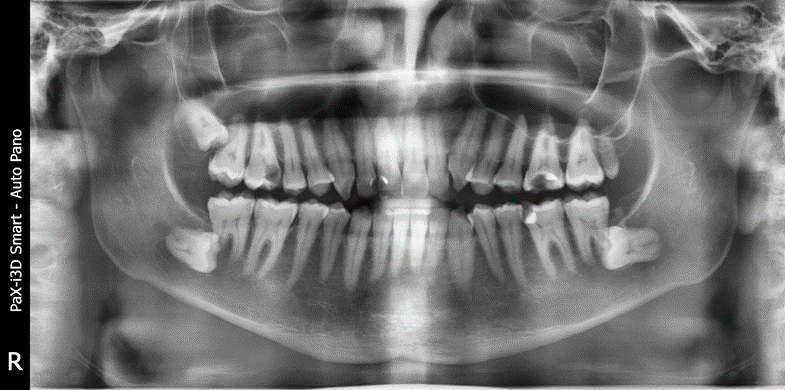

Ортопантомограмма (ОПТГ) — панорамный рентгеновский снимок обеих челюстей Ильи

Саму клиническую картину мы получили, только когда сделали томограмму и прицельные снимки.

На первом визите мы ревизировали зуб с кистой, и всё с ним стало понятно. А для того, чтобы разобраться с кариесом, было сделано достаточно много прицельных снимков.